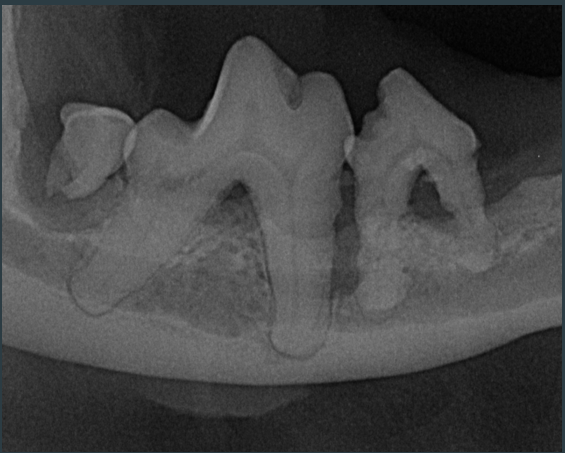

▲院内新进牙科DR设备之一

▲部分牙科DR效果展示图(可左右滑动)

什么是DR?

DR检查是影像科常用的一种检查方法,它又称为数字化X射线摄影系统,相对于传统的拍片子检查,它的辐射量更小,检查的时间更短,片子的质量也更高